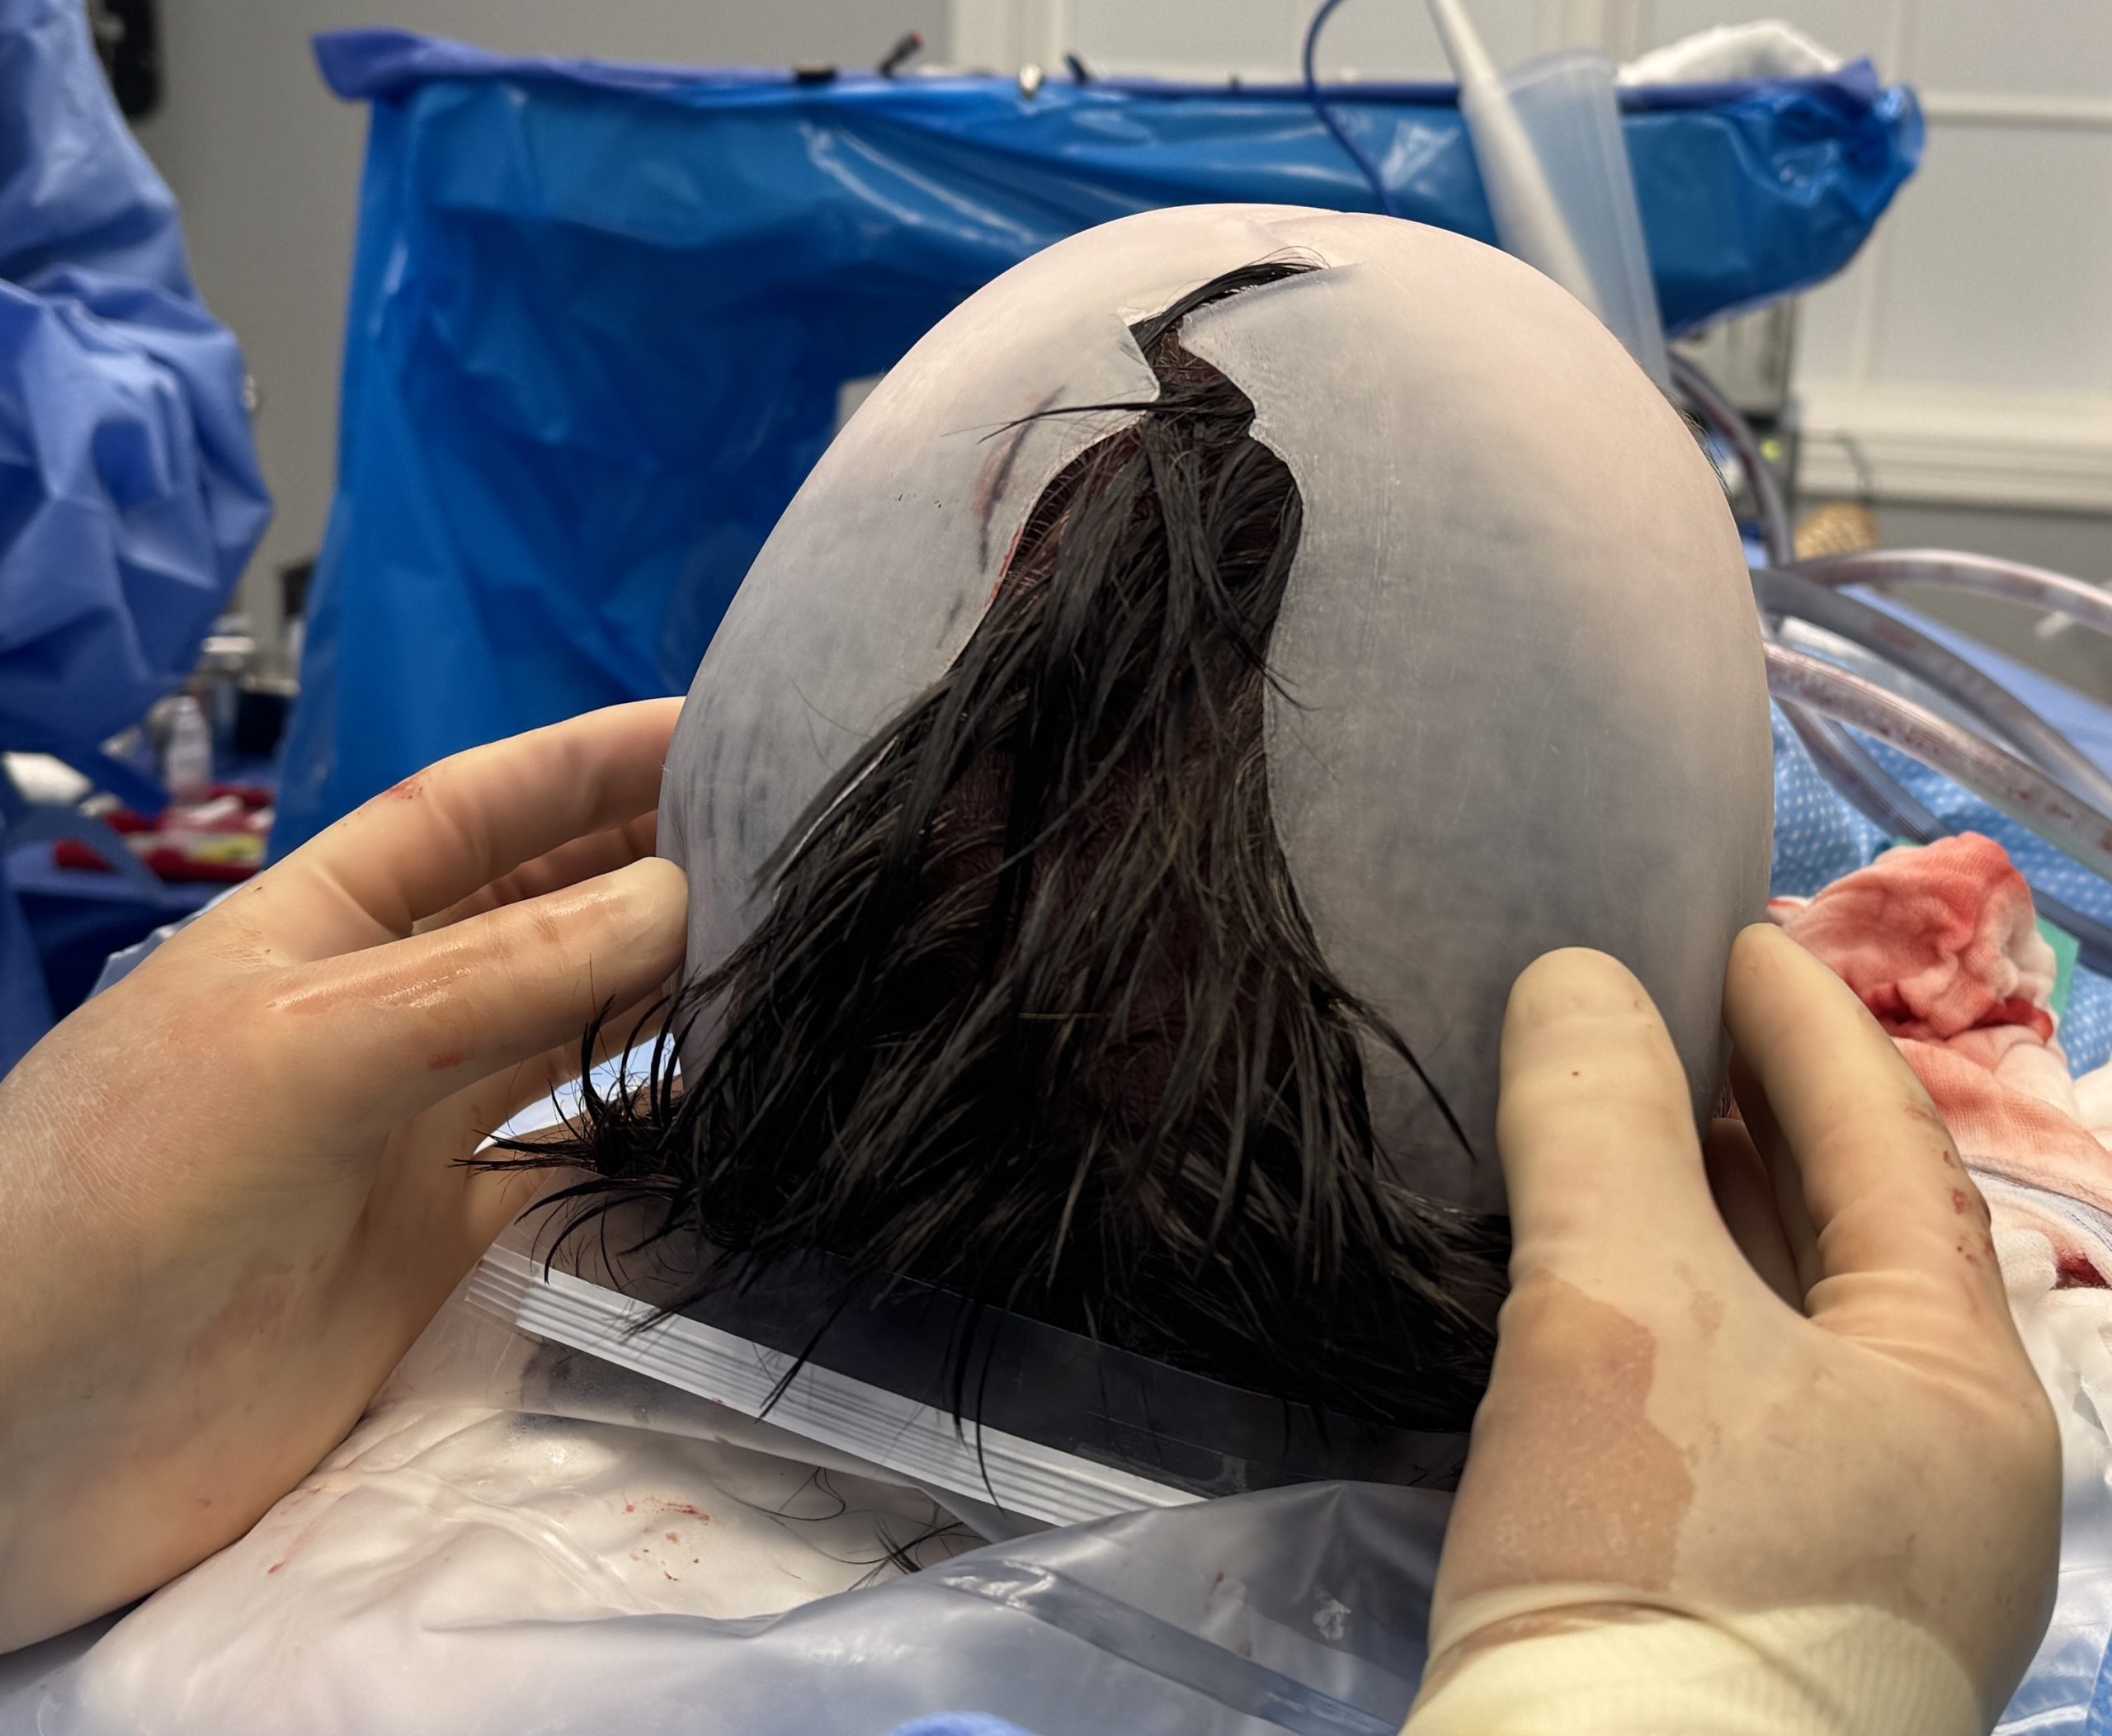

Long haired male with desire to augment a congenital flat back of the head.

Placement of custom back of head skull implant without trimming or shaving any hair. The incision was hard to find postop.

Long haired male with desire to augment a congenital flat back of the head.

Placement of custom back of head skull implant without trimming or shaving any hair. The incision was hard to find postop.